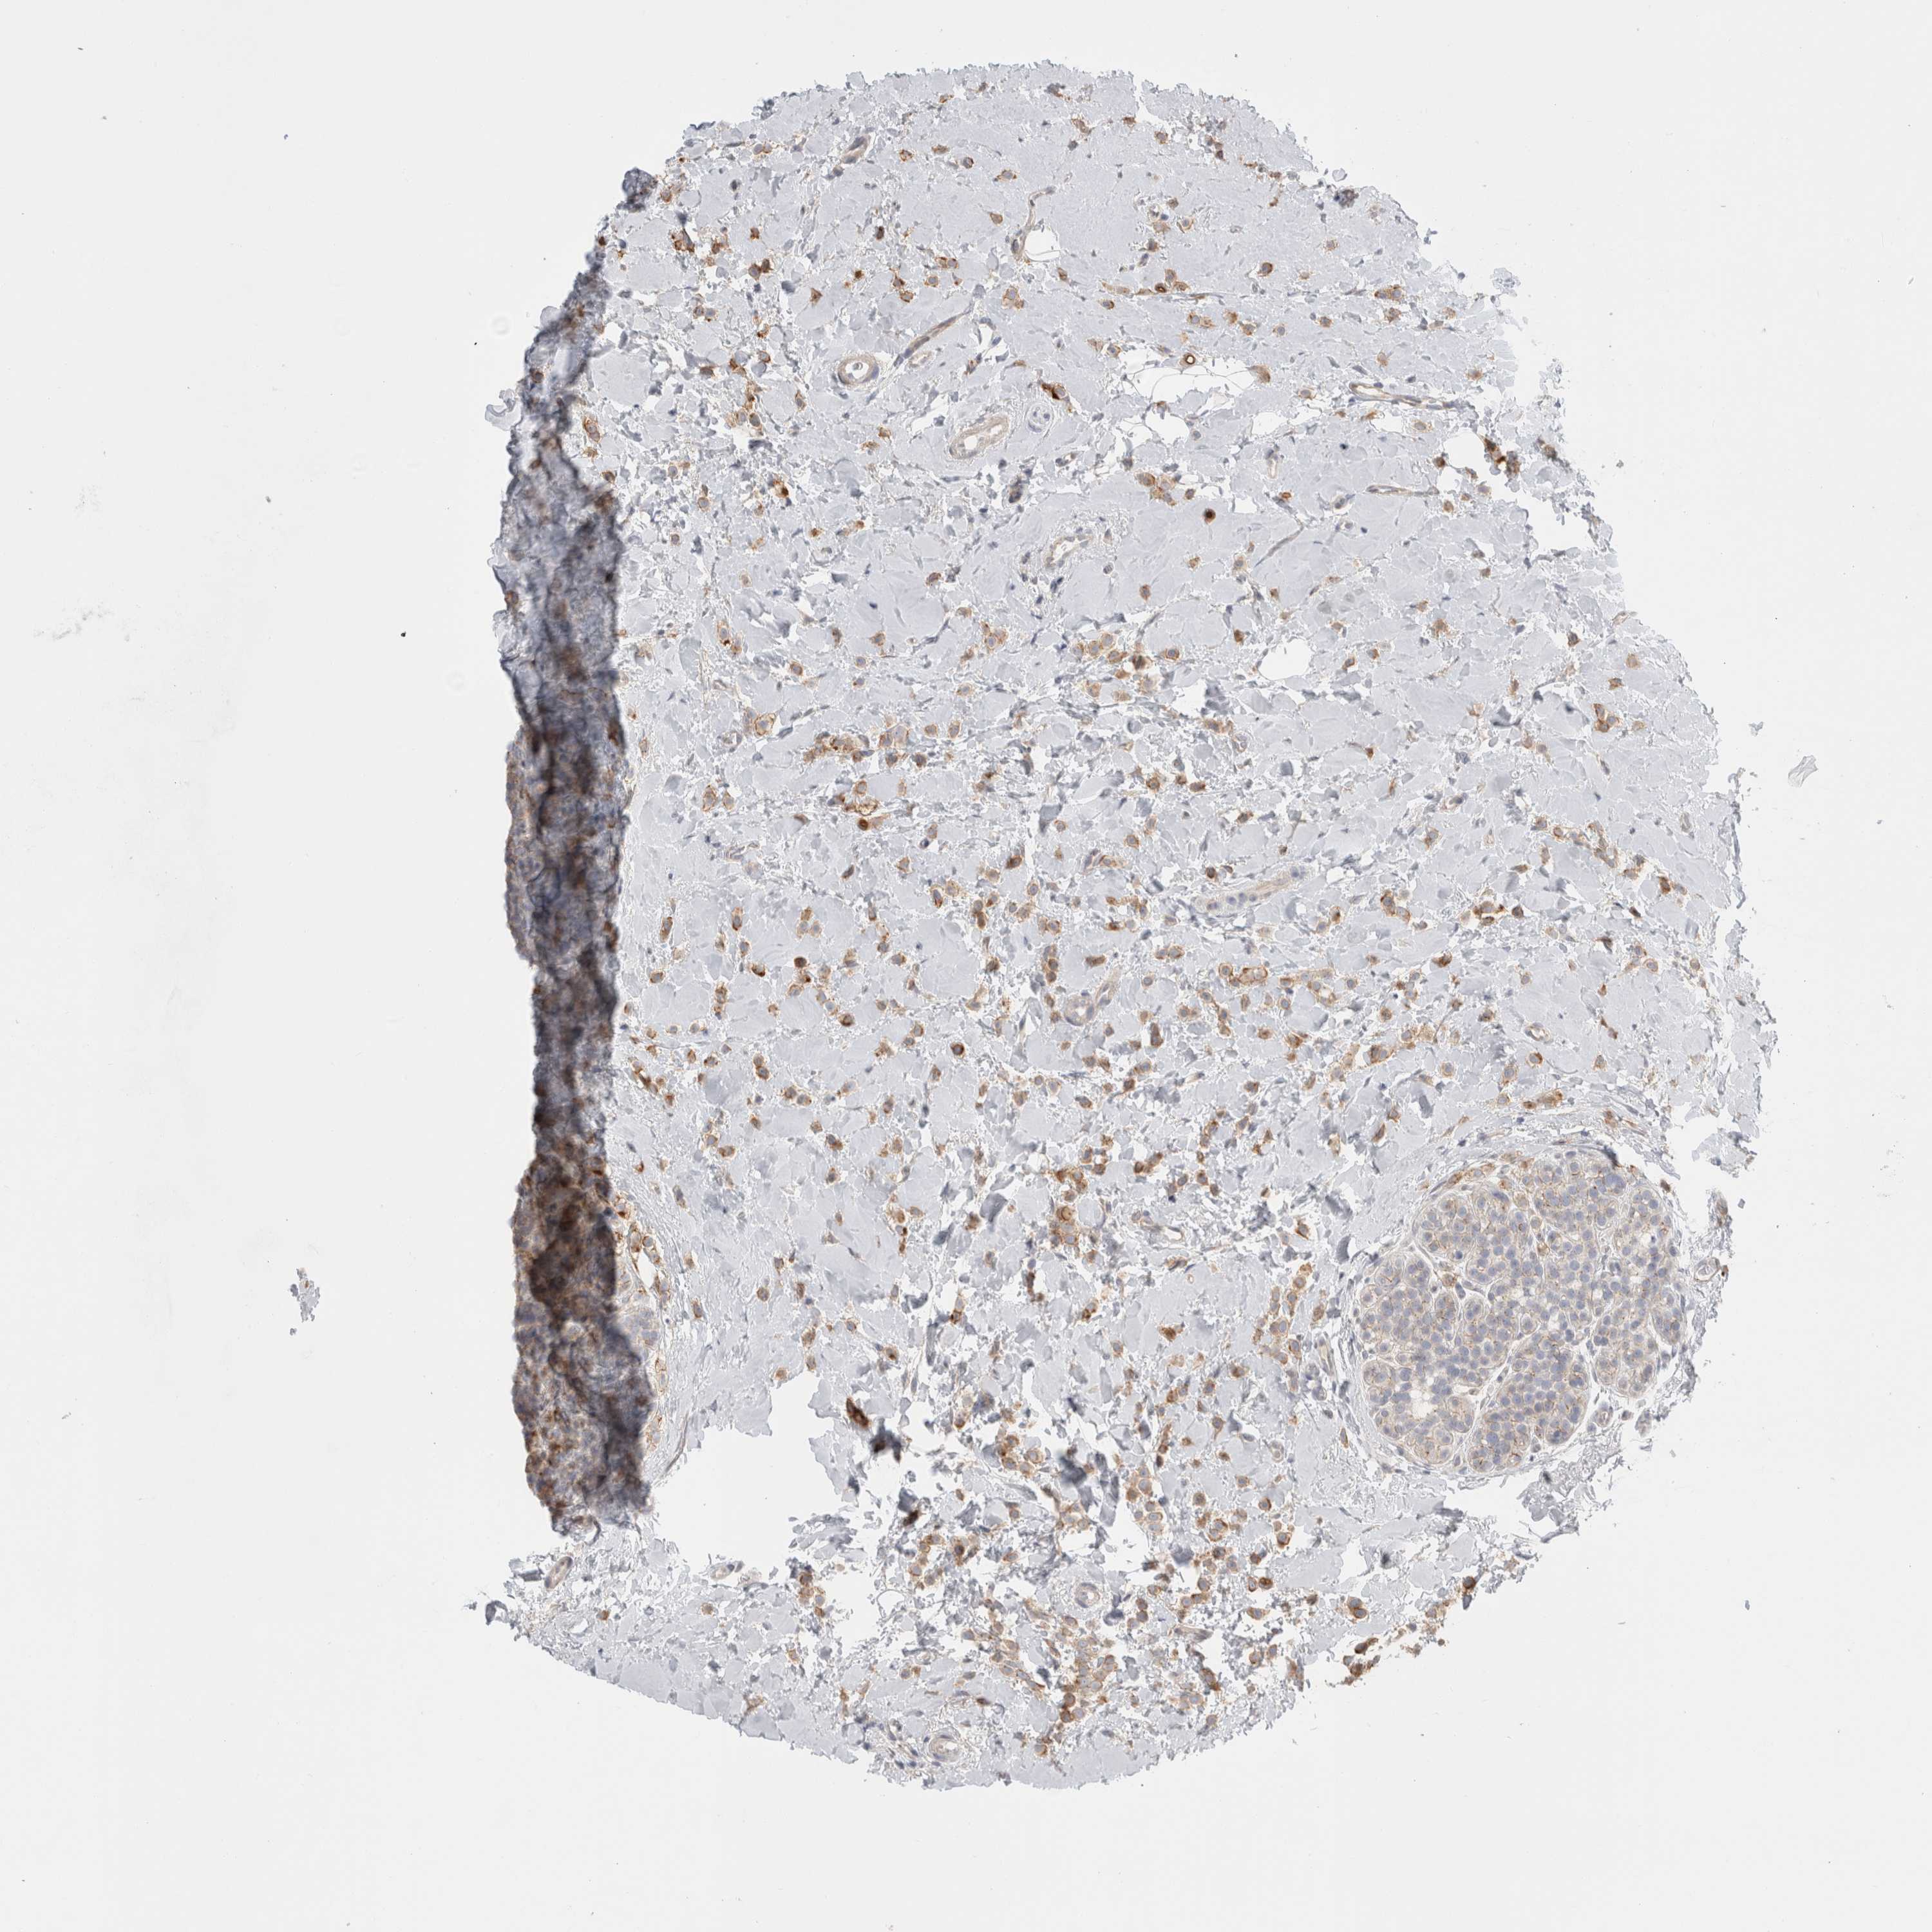

CANCER BREAST CANCER Show tissue menu

BRCA TCGA BRCA VALIDATION PROTEIN EXPRESSION